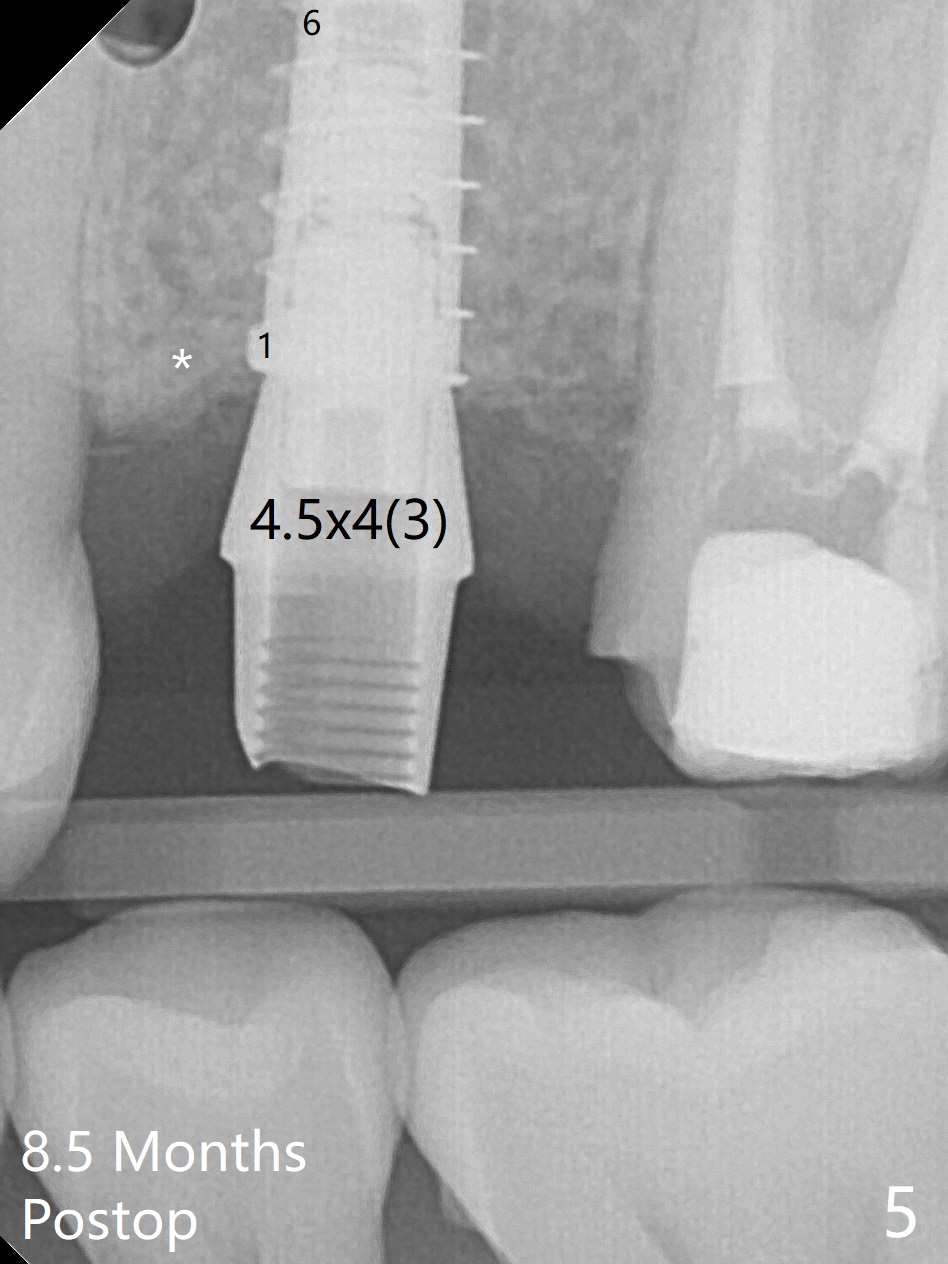

Due to misinterpretation of drill sequence, osteotomy is overprepared in depth (1.5 to 3 mm). When a 4x11 mm dummy implant is placed with > 50 Ncm (Fig.1,2), over placement is ignored. A 4x13 mm final implant is placed with fairly good torque, but it is deeper than expected. When it is backed up, primary stability is lost, in spite of placement of allograft in the osteotomy. Final torque is 15 Ncm. When a 4.5x4(2) mm abutment is placed, the underlying implant turns (Fig.3). A splinted provisional is fabricated at #13 and 14. RCT is retreated 5 months postop (Fig.4 *). An abutment with longer cuff is placed before impression (8.5 months postop, Fig.5). When the crowns of #13 and 14 are delivered, the former looks short and noncosmetic, although the gingiva will grow downward to close the gap (Fig.6). Ideally the gap should be closed with porcelain with overhang (Fig.7).